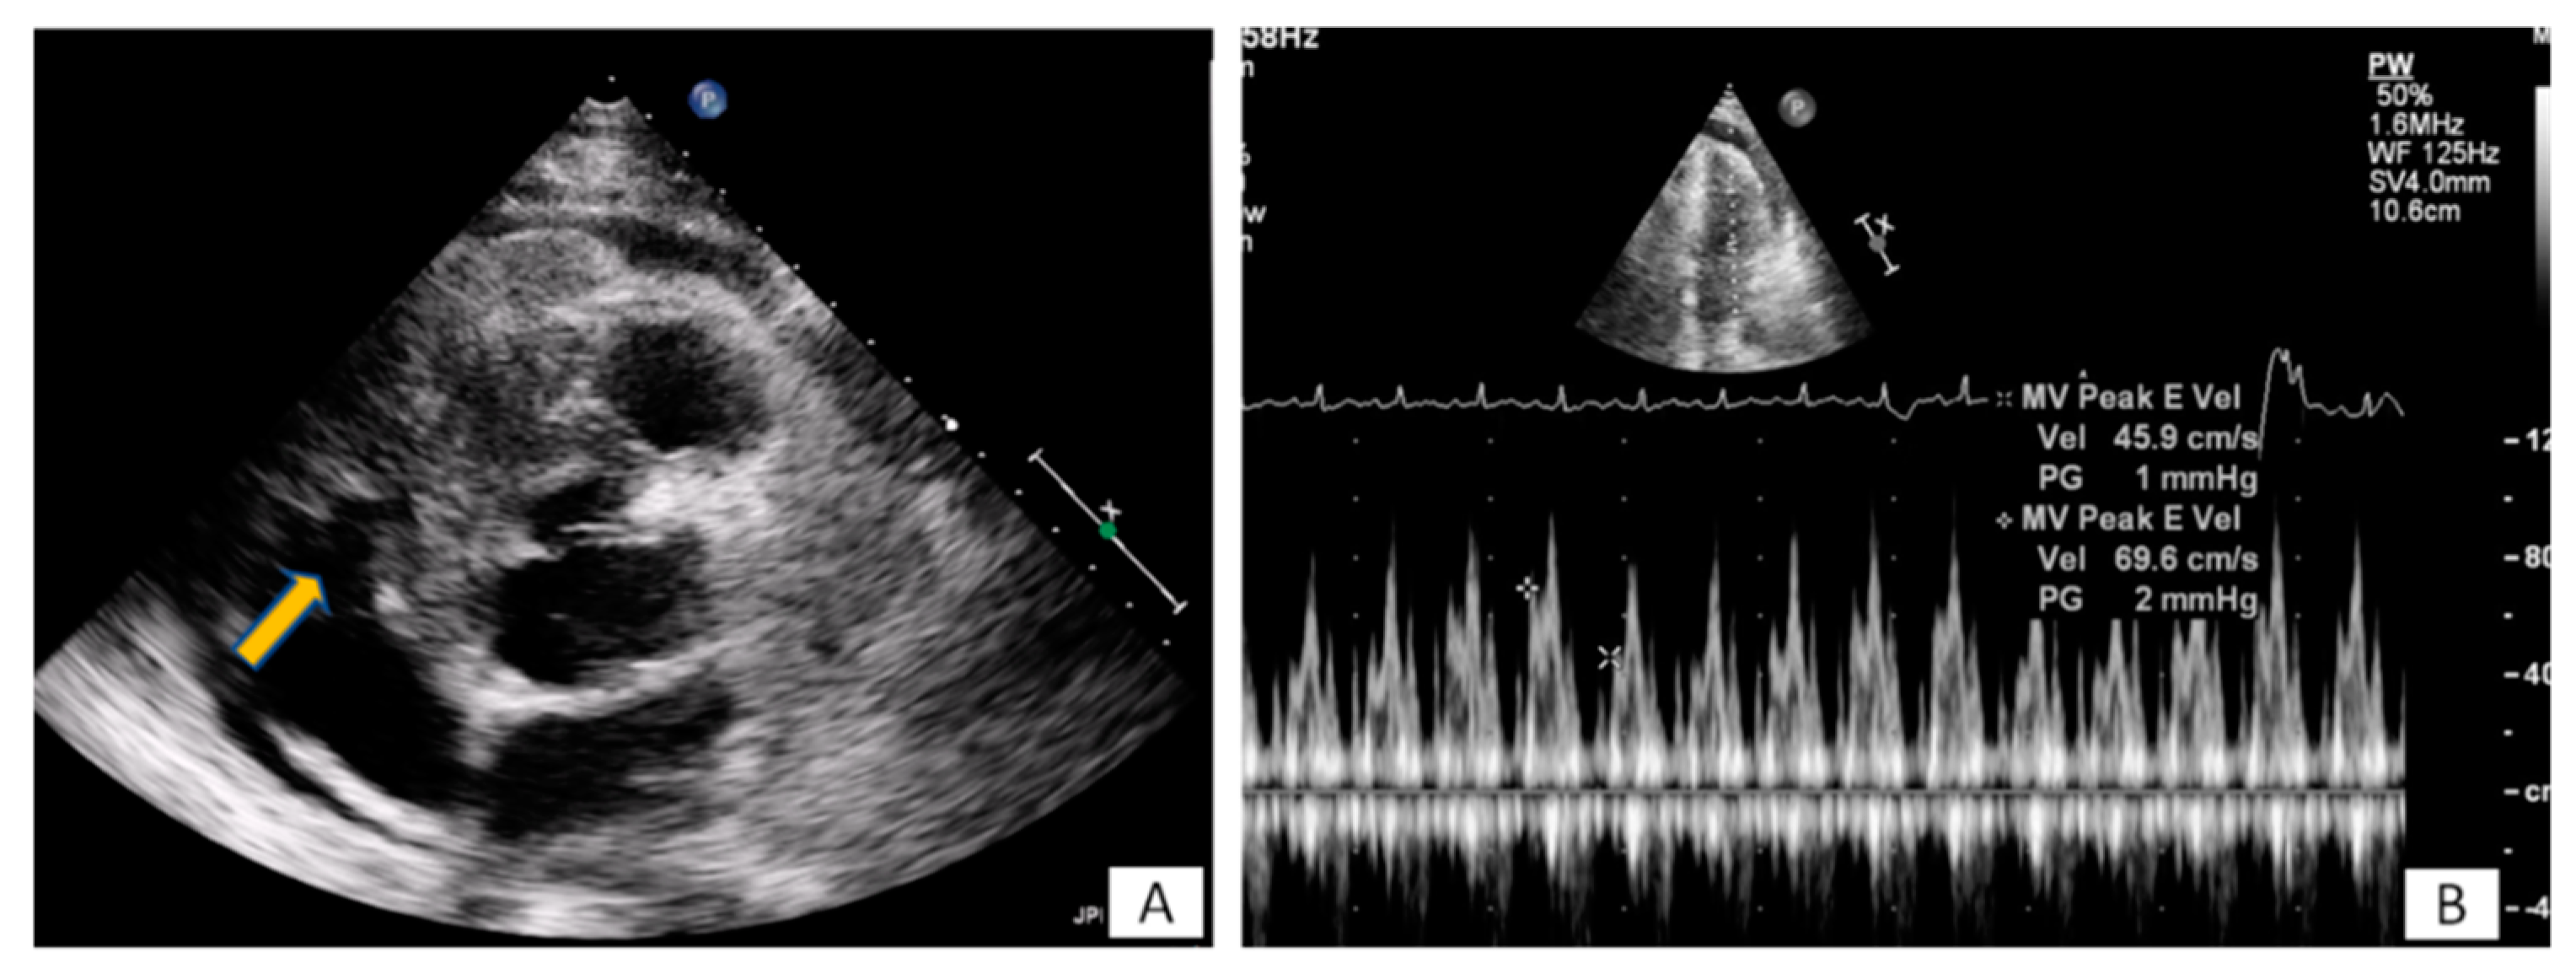

3.1. Transthoracic Echocardiography